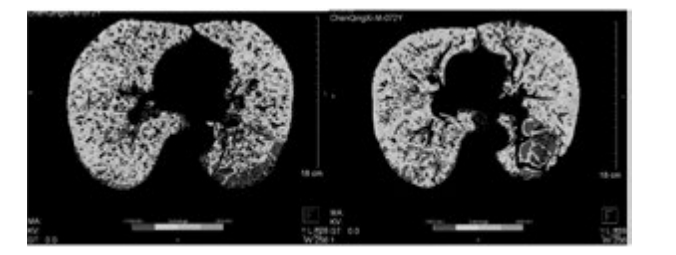

例1患者行干細胞移植前后肺部 CT 檢查

下圖為雙源CT肺實質(zhì)分析軟件,深藍色表示CT值在-1000 至-951,治療后較治療前深藍色面積明顯縮小。

雙源CT肺實質(zhì)分析軟件

從表3、表4提示,CT 值在-1000 至-951 比例有所下降,Class4( % ) 亦明顯下降,故肺氣腫較治療前好轉(zhuǎn)。